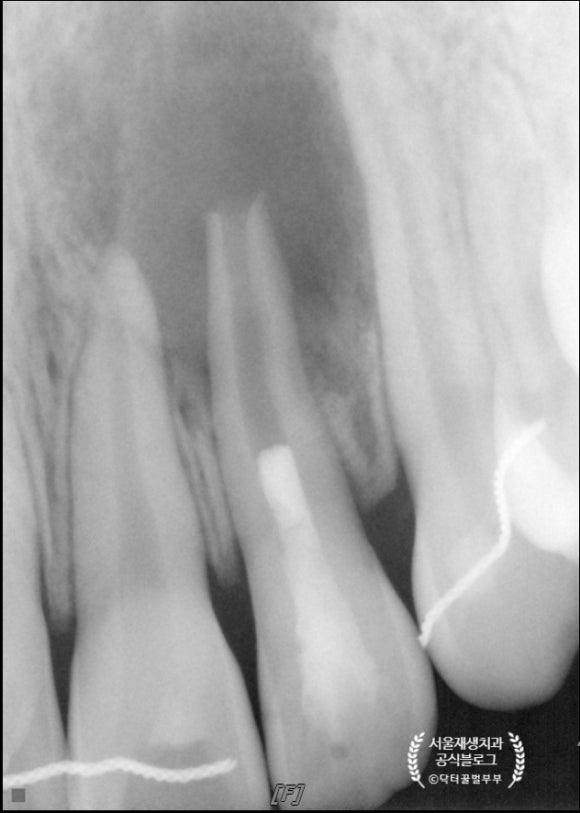

치료 후 7 개워이 지났습니다.

치아 뿌리는 더욱 두꺼워졌고, 병소도 거의 다 사라졌습니다.

이제 시간이 더 지나면 뿌리는 더욱 성숙해질테고, 병소였던 부위도 보다 밀도가 높은 뼈로 재생될테지요^^